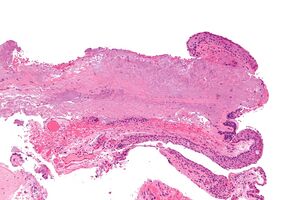

علم الأمراض

Pterygium in the conjunctiva is characterized by elastotic degeneration of collagen (actinic elastosis[12]) and fibrovascular proliferation. It has an advancing portion called the head of the pterygium, which is connected to the main body of the pterygium by the neck. Sometimes a line of iron deposition can be seen adjacent to the head of the pterygium called Stocker's line. The location of the line can give an indication of the pattern of growth.